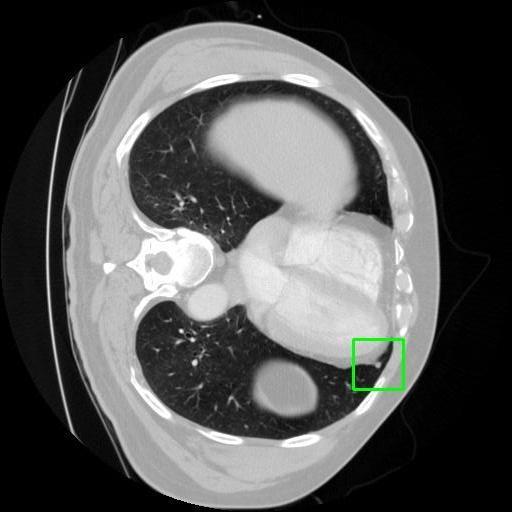

We developed an AI-based system using deep learning models for analyzing lung CT scans to detect and classify pulmonary nodules. We chose the YOLOv11 architecture for its enhanced object detection capability and adapted it specifically for medical imaging, incorporating pixel-level precision and severity classification.

Classification into three severity levels with colored bounding boxes.

Maintaining performance on small, complex features like micro-nodules tested the limits of traditional object detectors.

Designed a severity classification system that categorizes nodules into null, moderate, and severe using colored bounding boxes, assisting in rapid clinical decision-making.